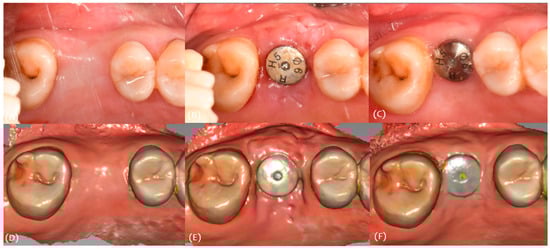

3.1. Case 1

3.2. Case 2